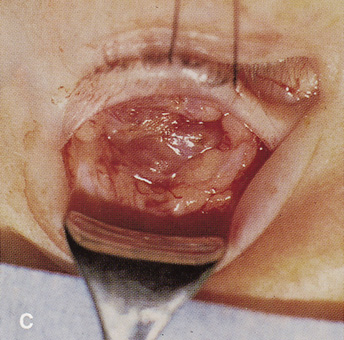

HISTORY AND PHYSICAL EXAMINATION A wide range of signs and symptoms may alert the ophthalmologist to involvement of the orbit by a pathologic process. These include proptosis or globe displacement; compressive optic neuropathy with visual field or visual acuity loss; refractive changes such as progressive hyperopia, restricted eye movements, and diplopia; optic disc changes, including pallor or edema; and fundus changes such as choroidal folds. These manifestations may be the consequences of a primary intraorbital disease or may occur secondary to involvement of the orbit by a process extending from the overlying soft tissues, periorbital sinuses, or intracranial cavity. All patients with suspected orbital pathology should have a thorough ophthalmic history and physical examination. Detailed questioning about the nature, onset, and progression of the chief complaint is necessary to formulate a differential diagnosis. Previous ocular and general medical history related to diseases, operations, medications, and family history should be obtained. A general review of systems will identify risk factors for related systemic diseases, such as hyperthyroidism, metastatic cancer, or lymphoma. A complete examination of the eye and periocular tissues is essential. Abnormal protrusion or displacement of the globe, extraocular motility disturbances, soft-tissue changes, and decreased corneal or periorbital cutaneous sensation should be specifically sought. Special attention always should be directed to evaluation of optic nerve function. Visual acuity testing alone is not sufficient because visual acuity often is preserved initially in patients with compressive optic neuropathy. All patients should be examined closely for detection of an afferent pupillary defect, abnormal color vision, or loss of contrast sensitivity. Formal perimetry should be performed to rule out peripheral field loss. If the presentation has been gradual, evaluation of old photographs may help establish the time course of the pathologic process. In selected cases, appropriate blood work to help identify orbital inflammatory or neoplastic processes also should be obtained. ORBITAL IMAGING Valuable information about the nature and extent of an orbital pathologic process is provided by imaging studies such as computed tomography (CT) scan, magnetic resonance imaging (MRI), and orbital echography. Better spatial resolution, ready accessibility, and lower cost make CT the preferred choice for orbital imaging in most cases. Orbital fat provides a natural contrast between most adjacent orbital structures on CT scanning, and orbital bones are visualized well. Computed tomography is essential for evaluation of the orbital bones because they cannot be imaged with MRI. Direct coronal or sagittal images are important to identify the relationship of a lesion to the optic nerve so that the surgical approach can be planned to avoid traversing the optic nerve (Fig. 1). Newer multislice helical CT scanners allow continuous acquisition of data so that a single rapid pass allows formatting in axial, coronal, and sagittal planes. Multislice CT provides shorter examination times with reduced motion artifact and radiation exposure when compared with conventional CT. Magnetic resonance imaging is useful in selected cases, especially when evaluating the orbital cranial junction. Significant bony artifact and a lack of orbital fat in the orbital apex make CT scan resolution of the orbital apex structures poor. Because cortical bone has low signal on MRI, there is no bone artifact when viewing the orbital apex on MRI. The lack of intervening fat in the apex to provide contrast is overcome on MRI because contrast is provided by the individual nuclear characteristics of each tissue so that the orbital apex structures are visualized well. Consequently, conditions that affect the optic nerve and chiasm, such as optic nerve meningioma and glioma, generally are evaluated with MRI rather than CT scan (Fig. 2). Use of a contrast agent such as gadolinium can further enhance the T1 signal intensity of lesions and is particularly helpful in imaging areas where there has been a breakdown in the blood–brain barrier. Because orbital fat produces a bright signal on T1-weighted images, orbital MR usually is performed with “fat suppression” to prevent masking of lesions. However, incomplete fat suppression can produce artifacts that may be misinterpreted as abnormal enhancement. A few other orbital conditions are better visualized with MRI than CT scanning.1–3 Often, organic foreign bodies, such as wood, are not imaged well with CT scan. These foreign bodies often are visible with MRI. However, care must be taken when imaging any metallic intraocular or intraorbital foreign body because the strong magnetic field of the MR scanner may cause the foreign body to shift position and damage surrounding structures. In some tumors and vascular anomalies, high blood flow is appreciated on MRI. This is caused by a lack of signal, known as a flow void, created by blood flowing rapidly through larger vessels. Tumors that originate in the brain and extend into the orbit secondarily, such as sphenoid wing meningioma, also are visualized well with MRI. However, bony detail and calcification within the meningioma are not imaged well. In unusual circumstances such as this, CT scan and MRI may prove to be complementary, and both techniques may be required to fully evaluate the orbital disease process. Orbital echography can provide useful information in the evaluation of orbital disorders. Because each tissue has its own acoustic characteristics, echography can provide a high degree of tissue contrast. Spatial resolution also is quite good. In some situations, echography can provide information not available on CT scan or MRI. These instances include detection and measurement of blood flow4 and intraoperative localization of small foreign bodies.5 Orbital echography requires specialized equipment and a large amount of expertise to obtain the detailed information that is readily available with CT scan or MRI; consequently, its use has decreased. Recent advances in orbital imaging have been summarized by Lee and colleagues.6 |